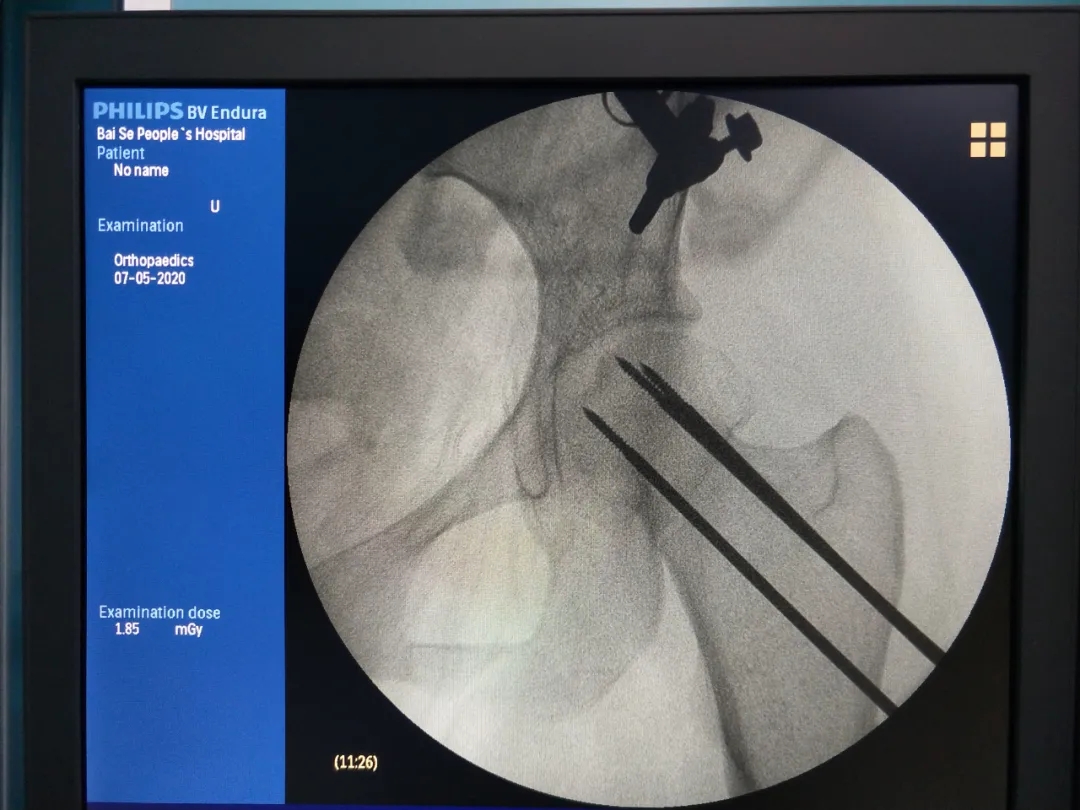

开展天玑?骨科手术机械人辅助下股骨颈骨折经皮倒三角形空心加压螺钉内牢靠术。。。。。。天玑?骨科手术机械人精准定位,,,,,,乐成置入3枚空心钉,,,,,,真正做到创口小,,,,,,疼痛轻,,,,,,恢复快,,,,,,出血小,,,,,,患者住院时间短,,,,,,在机械人导航系统辅助下,,,,,,显着提高了手术准确性和清静性,,,,,,术后第一天,,,,,,患者功效恢复。。。。。。

术中导针进针位置(正位片)

在机械人精准辅助下操作